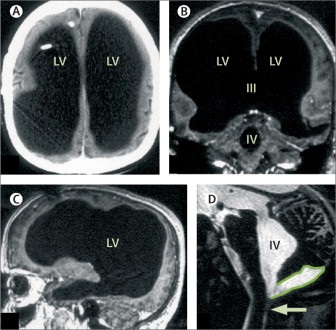

Figure 2: Massive ventricular enlargement, in a patient with normal social functioning: (A), (B), (C) MRI with gadolinium contrast at different cross-sections; (D) T2-weighted MRI. LV=lateral ventricle. III=third ventricle. IV=fourth ventricle. Arrow points to Magendie foramen. The posterior fossa cyst is outlined in (D). The figure is taken from (Feuillet et al., 2007).

Although dendrites and axon terminals of neurons of the brain penetrate through all brain space densely, there are spaces relatively free of the nervous filaments. These spaces are ventricles of the brain filled by the cerebral liquid. In medical practice there is a case where a 44-year-old patient with postnatal hydrocephalus of unknown cause (Feuillet et al., 2007) showed via magnetic resonance imaging (MRI) that his brain had hypertrophied brain ventricles, Fig. 2. The deficit of the filamentous organization demonstrates massive enlargement of the lateral, third, and fourth ventricles, with a very thin cortical mantle and a posterior fossa cyst. Surprisingly, however, this patient possesses OK normal social functions, and has an intelligence quotient (IQ) of about 75. This example provides an indirect hint of the fact that the cerebral liquid, a slightly brackish water, has a direct relationship to cognitive functions of the brain.